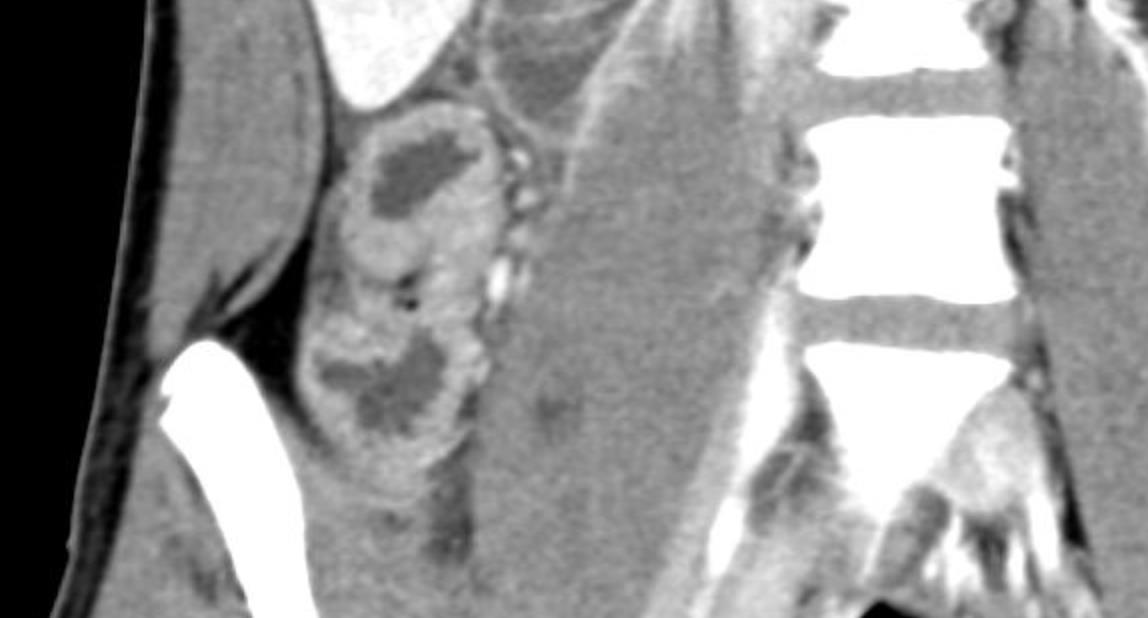

Abdominal abnormalities

Solid viscera abnormalities

Hepatomegaly

Echogenic kidneys

Splenomegaly

Hollow viscera abnormalities

Gallbladder wall thickening

Bowel wall thickening

Bowel dilation

Gastric distention

Urinary bladder thickening

Peritoneal abnormalities

Small ascites

Mesenteric abnormalities

Mesenteric lymphadenopathy

• Gastrointestinal (GI) symptoms (abdominal pain, diarrhoea and vomiting) are prevalent in MIS-C

• Abdominal pain in 62%

• Up to 90% any GI symptom

• Anumber of studies have described abdominal imaging findings including ascites, bowel wall thickening and mesenteric lymphadenopathy